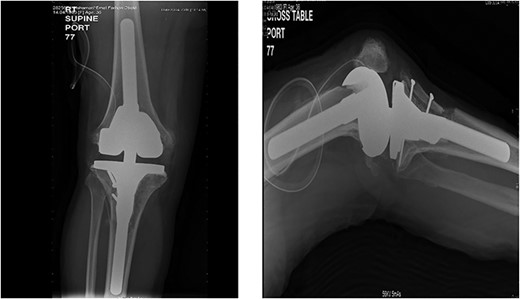

On the table, range of motion was 0–90°. Intraoperative image intensifier was used and demonstrated excellent position of the implant and the osteotomy site (Fig. 4).

Intraoperative image intensifier demonstrated position of the implant, screw and the osteotomy site.